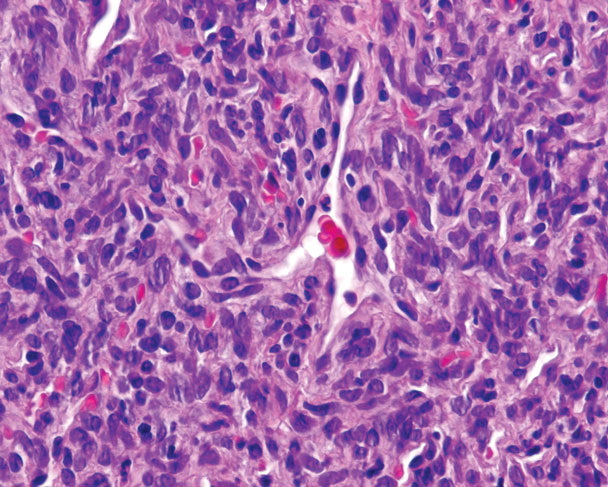

Hemangiopericytoma = ورم الخلايا الحولية